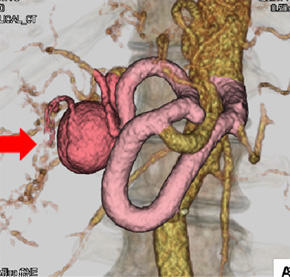

固有肝動脈瘤(赤矢印)に対する開腹血行再建